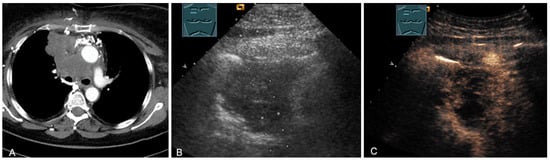

Figure 14.

A cystic mediastinal mass on CT (provided by Prof. Dr. Andreas H. Mahnken, Marburg, Germany) (A), B-mode US (B), and CEUS (C), surgically confirmed as a mediastinally located bronchogenic cyst.